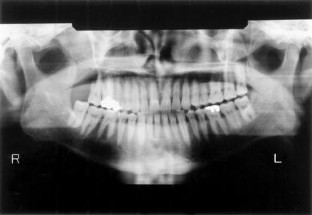

Bone formation is seen around the third molar even when the tooth is exposed to the oral environment due to overeruption. To determine if overeruption of the third molar with or without root exposure is related to the status of the exposure of other teeth in the mandible, using orthopantomographs, 424 third molars were studied in 371 patients who were over 41 years of age. The rate of overeruption and root exposure in third molars was measured, and its relationship to the number of teeth lost and the rate of root exposure in other teeth in the mandible was analyzed. Tooth loss in the group of third molars with overeruption without root exposure was greater than in that without overeruption or root exposure in men, whereas the relationship was not seen in women. We found that root exposures of other teeth in the group of third molars with overeruption without root exposure were significantly smaller than in those with root exposure in both genders. Third molars with overeruption without root exposure, in which bone formation was easy to observe for radiographic diagnosis, were correlated with periodontal health in the mandible, suggesting a component of precision determination for predicting resistance to periodontitis.

Fig. 1